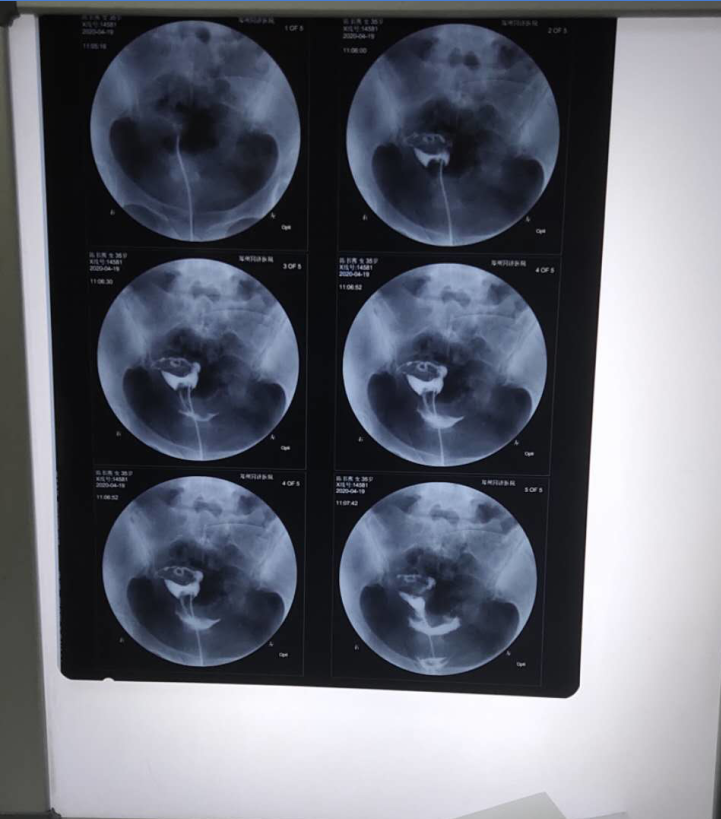

②排卵正常不怀孕,做妇科常规检查,看是否有炎症存在,有过妊娠史、阑尾炎、盆腔炎、宫腔手术、人工流产、生过一胎等要[检查输卵管是否通畅]。精子、卵子相遇受精全程在输卵管壶腹部进行,然后再输卵管蠕动下将受精卵输送到子宫着床发育。

提醒的是,造影是检查输卵管是否通畅的标准,是需要介入检查的,不可盲目的做。